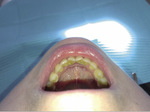

O ile stwierdzenie obecności kamienia naddziąsłowego (ryc. 1, 2) nie jest trudne, gdyż jest on widoczny w badaniu wizualnym i podczas zgłębnikowania, o tyle diagnostyka złogów poddziąsłowych może sprawić większy problem. Wzrokiem możemy ocenić tylko wysepki kamienia położone płytko, które uwidaczniamy za pomocą strumienia powietrza z dmuchawki unitu stomatologicznego. Zastosowanie lup oraz lepszego oświetlenia zwiększa czułość metody.[4] Jak podaje piśmiennictwo, w diagnostyce można wykorzystać sondę periodontologiczną. Cechuje się ona długą (10-12 mm) i odpowiednio zagiętą częścią pomiarową zakończoną kuleczką o średnicy 0,5 mm. Taka budowa zabezpiecza tkanki przyzębia przed traumatyzacją i umożliwia wyczucie nierówności na powierzchni korzenia.[5]